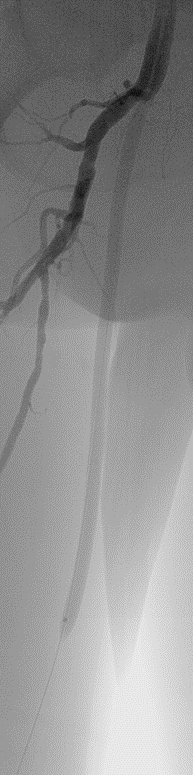

标准化操作流程(Tips)

开通:以内膜下技术为主,逆穿是常用且有效的辅助手段。

预扩:充分预扩张至关重要,需逐级使用高压球囊,最终达到 6mm 直径,以获得足够的管腔。

支架植入:遵循“由远及近”原则,先放置远端 DES,再覆盖中段 VB,最后处理近端。利用 Eluvia 的可调节性优化重叠。

后扩:常规使用 6mm 高压球囊进行后扩张,确保支架充分贴壁和管腔获得。

用药:术中术后必须充分抗凝,推荐“双通道”抗栓方案(如利伐沙班+阿司匹林),以模拟 bypass 的血流动力学效果。